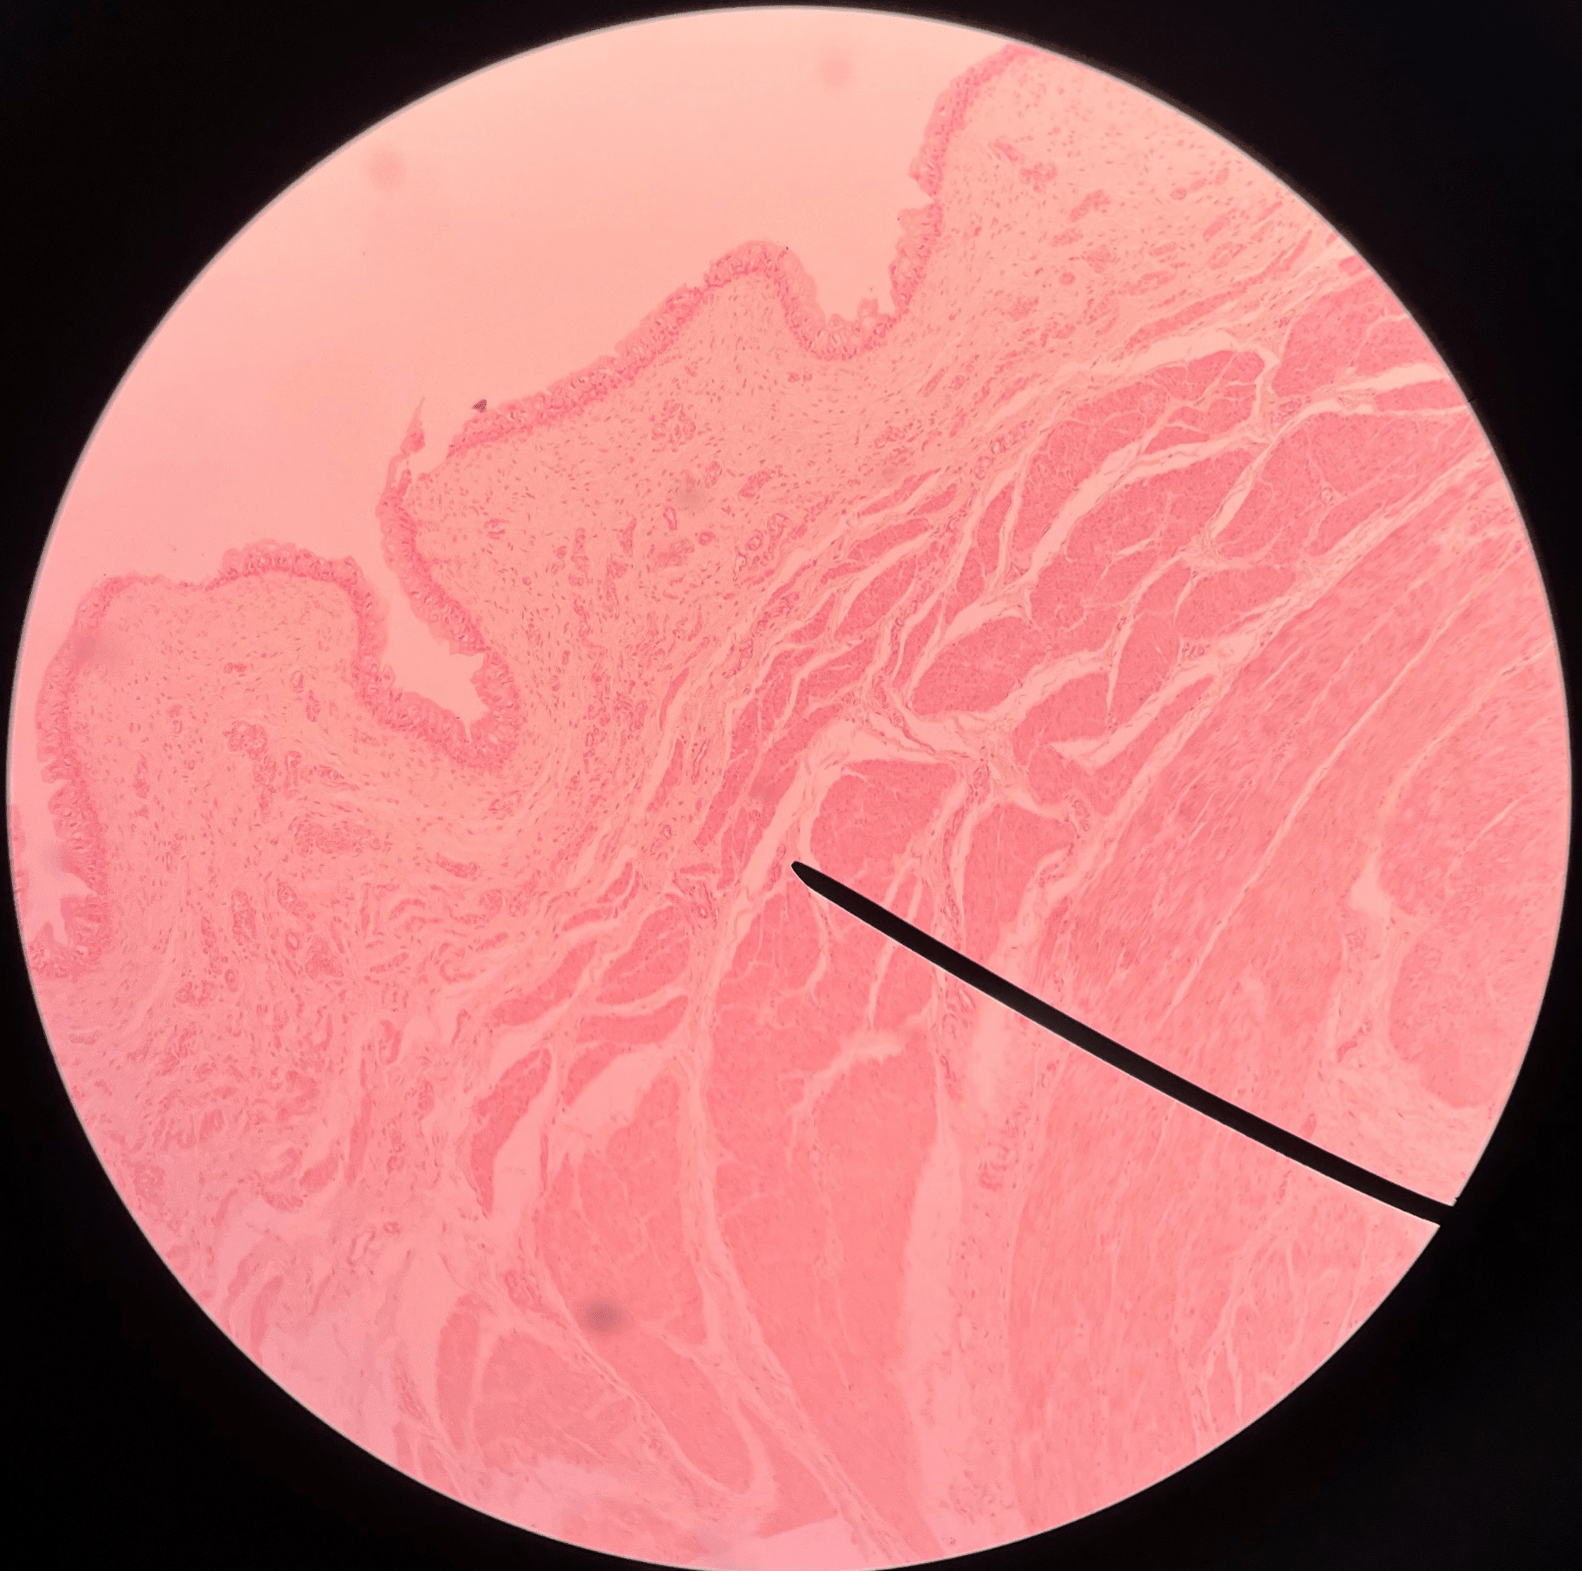

mucosa

• Slide histology of the bladder.

• The innermost layer of the bladder.

• Composed of urothelium.

• Faces the lumen of the bladder and is deep to the submucosa.

New cards

submucosa

• Slide histology of the bladder.

• A layer of the bladder.

• Superficial to the mucosa and deep to the muscularis.

New cards

muscularis

• Slide histology of the bladder.

• A muscular layer of the bladder.

• Also known as the detrusor muscle.

• Superficial to the submucosa.